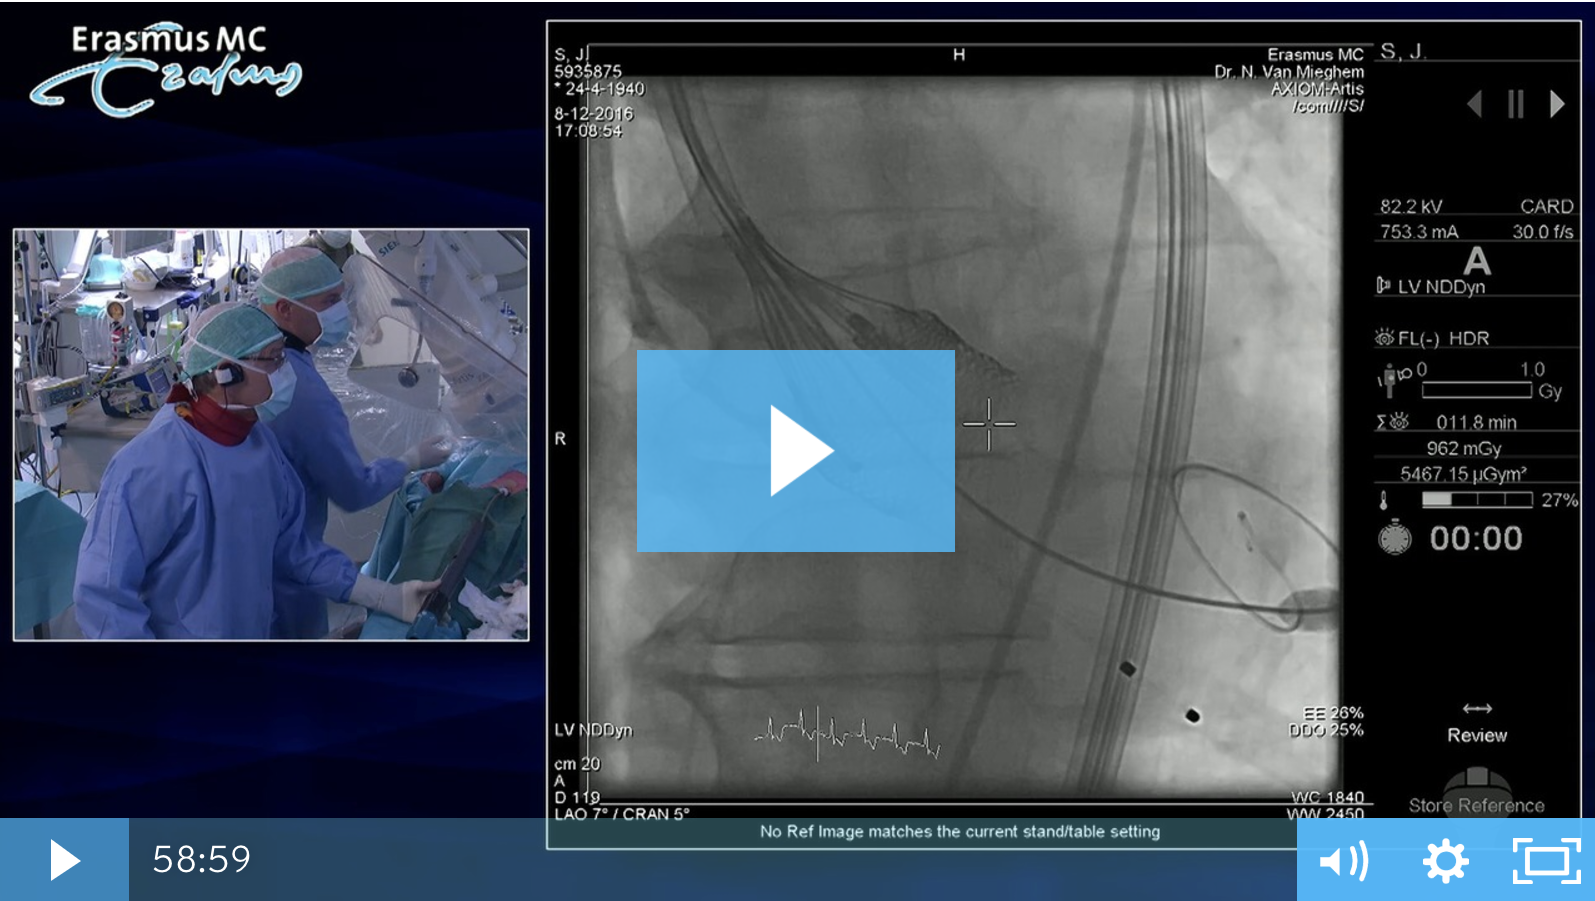

Live Case TAVR in bicuspid aortic valve stenosis

Dr Nicolas M. Van Mieghem , Thorax Centre, Netherlands performs TAVR in bicuspid aortic valve implantation, using the Boston Scientific Valve.

• Performing a TAVR implantation in a bicuspid valve

• Discussing specific valve features which impact outcomes

• Explaining implantation from A to Z